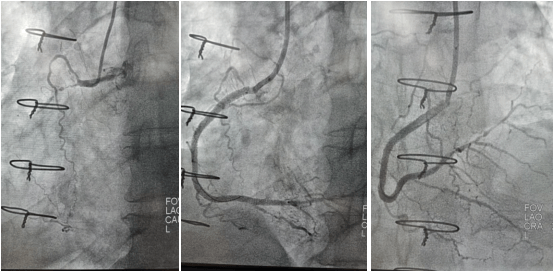

2022年9月16日行冠脈造影術(shù),造影結(jié)果示:左主干末端99%狹窄,LAD近段100%閉塞,LCX開口及近段95%狹窄,乳內(nèi)動(dòng)脈-左前降支血管通暢,RCA近段100%閉塞,大隱靜脈橋血管未見,考慮閉塞。

心血管病院吳棟梁院長(zhǎng)、CCU李新國(guó)副主任、心血管內(nèi)科二病區(qū)趙娟副主任、王端樂主治醫(yī)師、宋睿主治醫(yī)師介入團(tuán)隊(duì)造影后認(rèn)真研究患者的病情和影像資料,決定開通閉塞長(zhǎng)達(dá)11年的右冠狀動(dòng)脈,精確選擇器械,選擇同軸性及支撐力均好的指引導(dǎo)管,術(shù)中選用微導(dǎo)管輔助,軟、硬導(dǎo)絲結(jié)合等技術(shù),聚精會(huì)神、揮汗如雨,終于歷經(jīng)3小時(shí)的努力,成功前向開通右冠狀動(dòng)脈,精準(zhǔn)選擇由遠(yuǎn)及近“鋪設(shè)”通過性較好、長(zhǎng)度合適的支架 。

(術(shù)前術(shù)后對(duì)比)